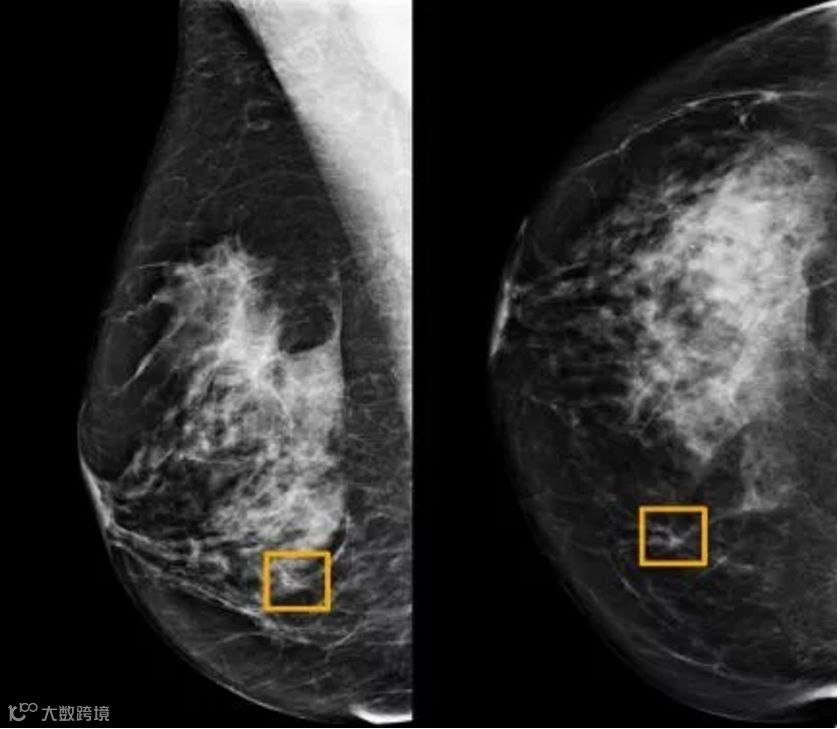

而这款深度学习AI模型可以通过筛查乳房X光图像来检测乳腺癌。研究人员利用两个大型数据集对该系统进行了测评。结果显示:出现假阳性与假阴性的概率都下降了,其表现优于另一项研究中的放射科专家。

Screening mammography aims to identify breast cancer at earlier stages of the disease, when treatment can be more successful1. Despite the existence of screening programmes worldwide, the interpretation of mammograms is affected by high rates of false positives and false negatives2. Here we present an artificial intelligence (AI) system that is capable of surpassing human experts in breast cancer prediction. To assess its performance in the clinical setting, we curated a large representative dataset from the UK and a large enriched dataset from the USA. We show an absolute reduction of 5.7% and 1.2% (USA and UK) in false positives and 9.4% and 2.7% in false negatives. We provide evidence of the ability of the system to generalize from the UK to the USA. In an independent study of six radiologists, the AI system outperformed all of the human readers: the area under the receiver operating characteristic curve (AUC-ROC) for the AI system was greater than the AUC-ROC for the average radiologist by an absolute margin of 11.5%. We ran a simulation in which the AI system participated in the double-reading process that is used in the UK, and found that the AI system maintained non-inferior performance and reduced the workload of the second reader by 88%. This robust assessment of the AI system paves the way for clinical trials to improve the accuracy and efficiency of breast cancer screening.